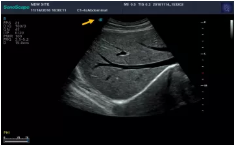

Mark點:每一把探頭都有一個mark點,是用于定位方向, mark點一側(cè)始終對應(yīng)著圖像S點(圖像箭頭標(biāo)識)一側(cè)。